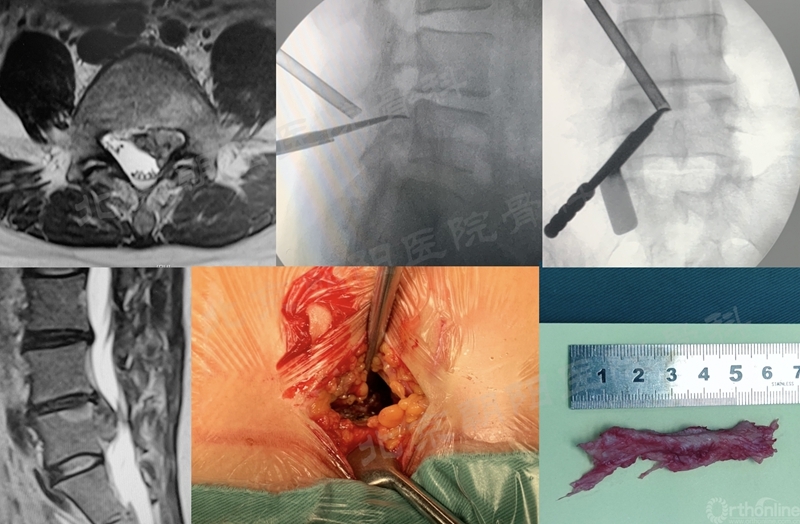

3、 硬膜损伤

#2例UBE,游离型LDH,未做好充分的上关节突内侧减压,误把硬膜当做突出的间盘,导致硬膜撕裂。及时转切开减压,取出大块髓核组织。